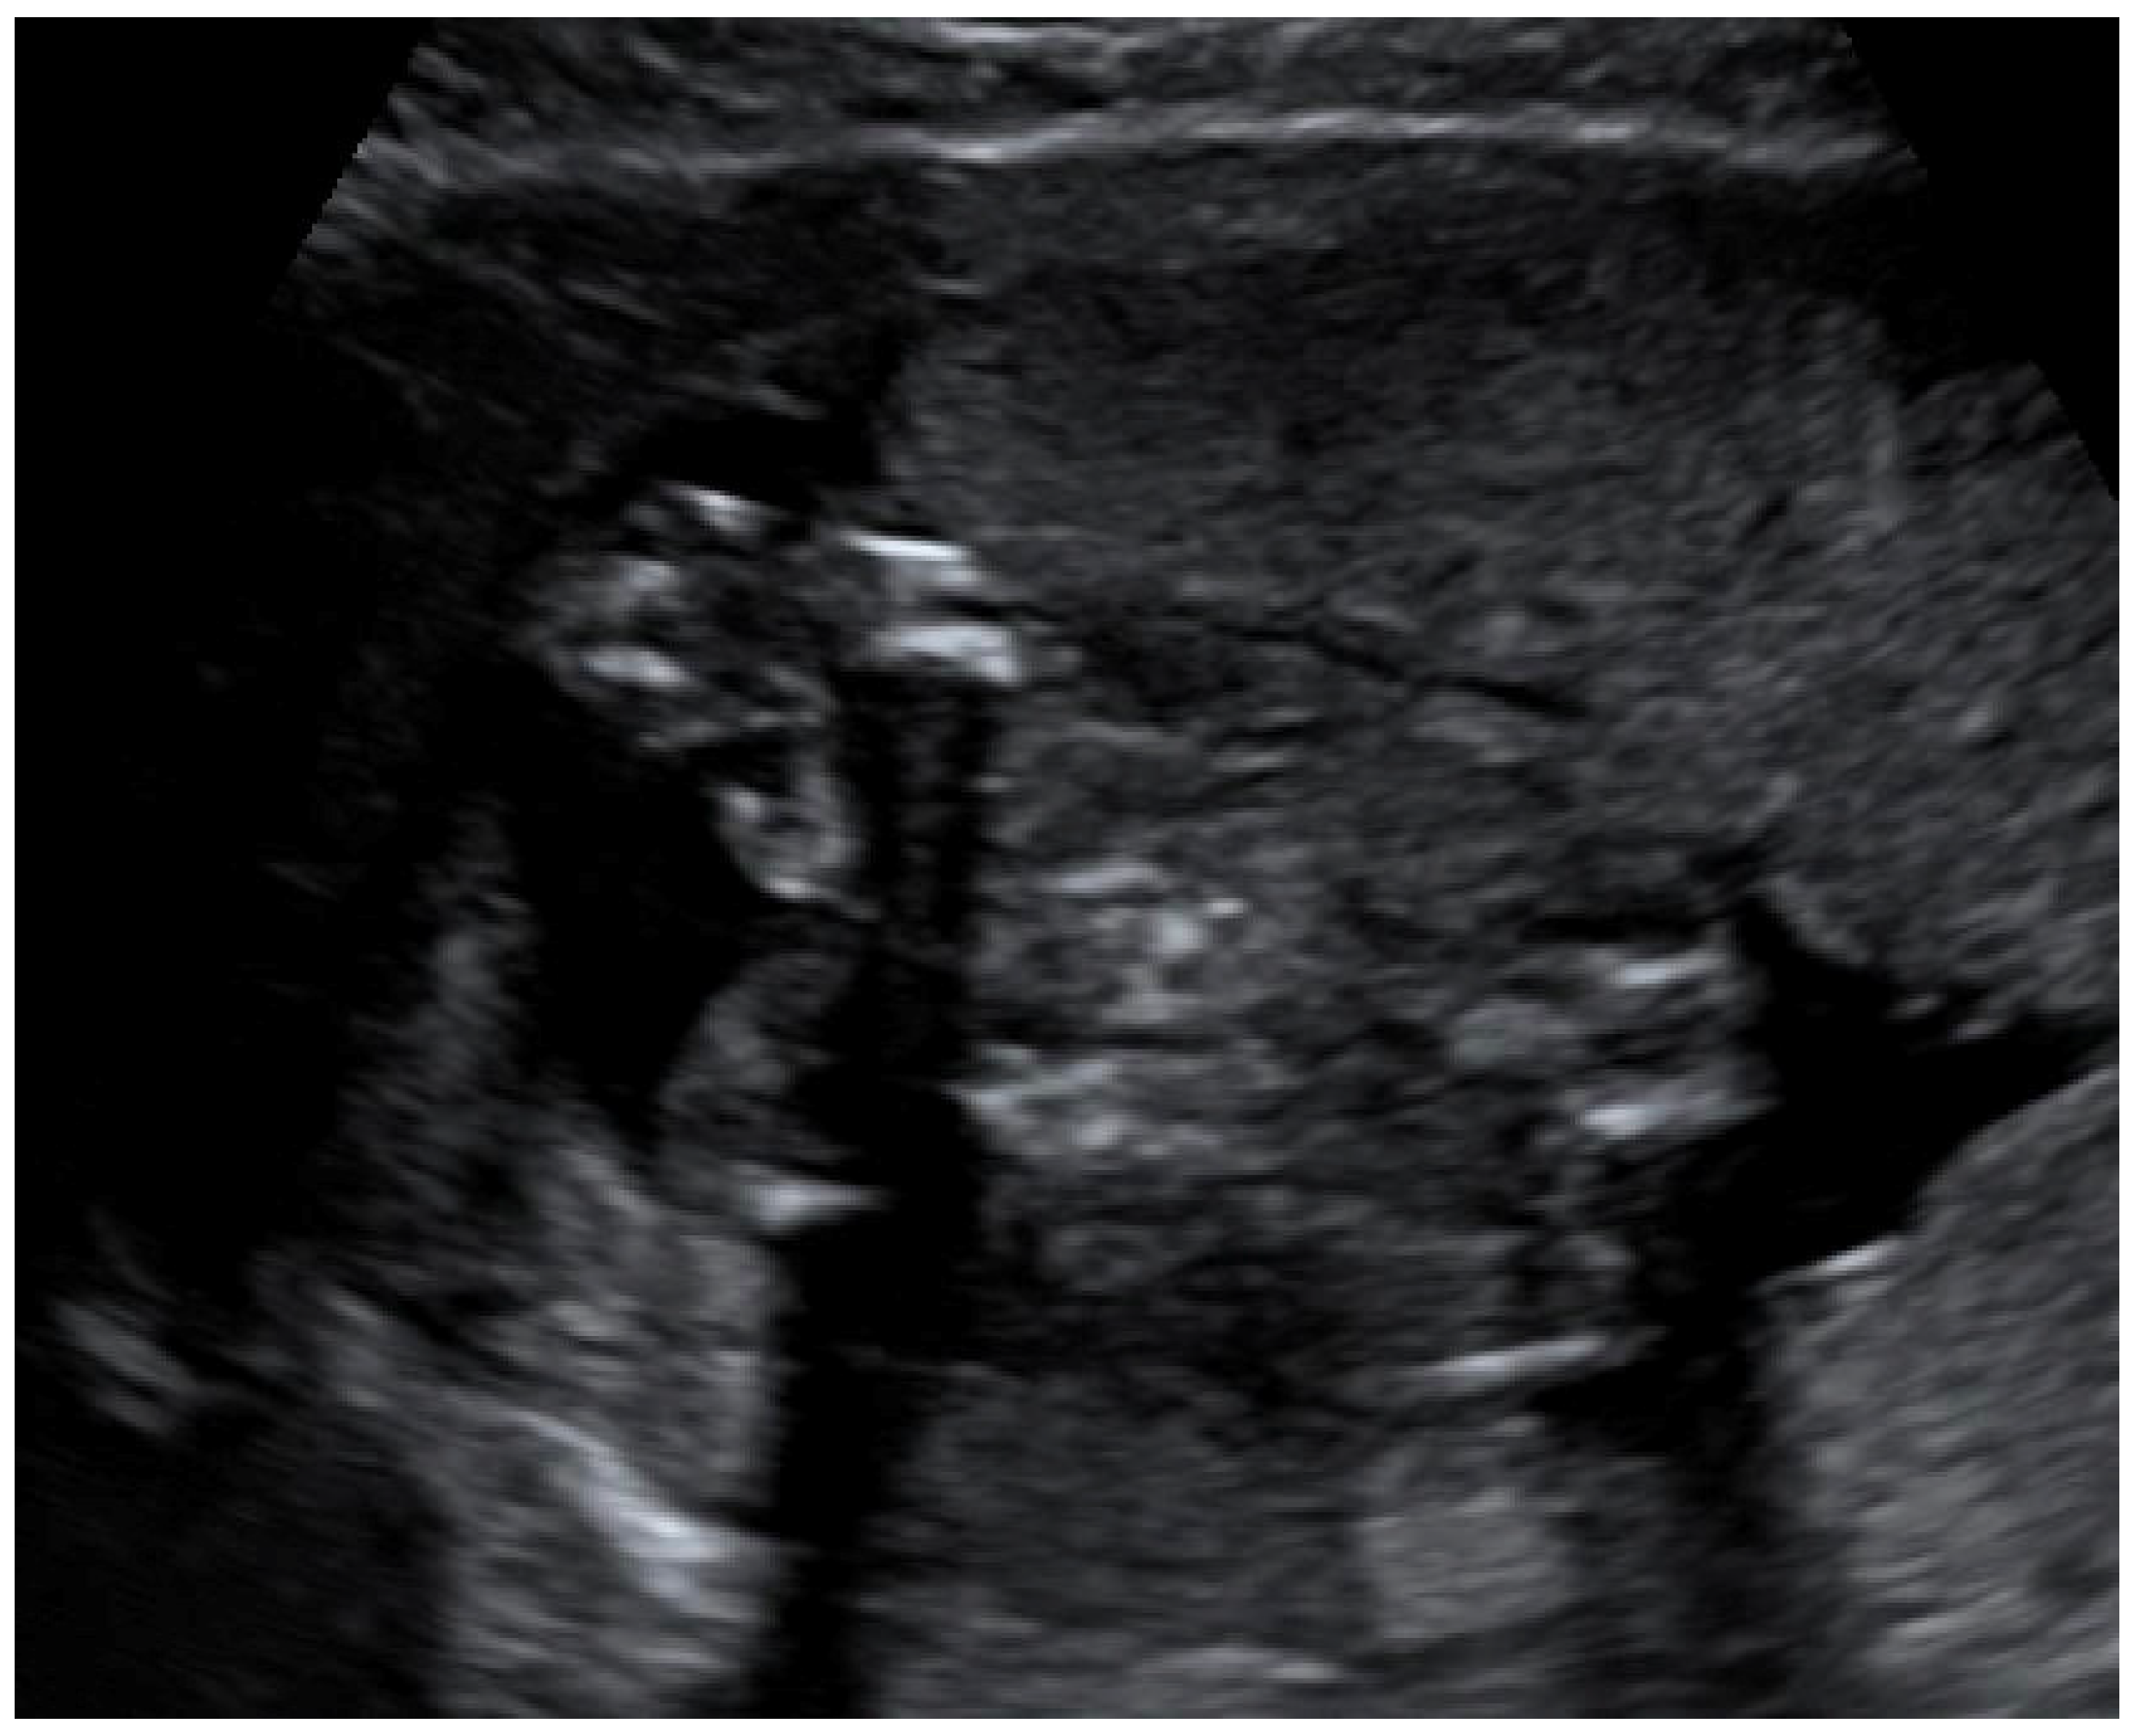

Congenital CMV fetal infection may be associated with a variety of CNS abnormalities. Those may be severe or mild; appear due to the early inflammatory, destructive, and obstructive processes of the brain infection; and directly influence fetal prognosis [60]. Ventriculomegaly (more than 15 mm), microcephaly (a decrease of less than two standard deviations), high echogenicity in the periventricular areas, and hydrocephaly may appear as severe intracranial signs. Increased cisterna magna (more than 8 mm), vermian hypoplasia, periventricular cysts, agenesis of the corpus callosum, lissencephaly, and porencephaly are often associated with congenital CMV infection [4,5,61]. Of these, ventriculomegaly and microcephaly are associated with the worst fetal prognosis. The mild cerebral findings related to fetal involvement include ventriculomegaly enlargement (10 to 15 mm) (Figure 3), intracranial calcifications (Figure 4), cysts of the choroid plexus, subependymal cysts, and intraventricular synechiae [62,63].

Figure 3. Dilation of the anterior and posterior horns of the lateral and third ventricles.